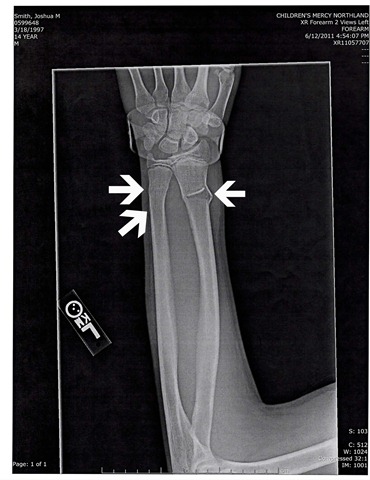

Of course there is always a monkey wrench in the best thought out plans, right? Sunday evening my 14 year old, Joshua, wrecked his bike and broke both bones in his arm in 3 places total. Yes… on a Sunday (don’t things like this always happen on the weekends at your house?). So off to the local children’s hospital urgent care center we went.

Because of the amount of pain he was in, we were able to be seen fairly quickly. Poor Josh could not straighten out his wrist, it was stuck in an arched position and he could barely wiggle his fingers. After some poking and prodding and a few x-rays we began the waiting game. The physician there put in a call to ortho because she wasn’t sure how they would want to procede.

So I am going to try to make a long story short. They splinted him and told us to make an appointment with ortho the next week. The next morning his fingers looked like sausages and he needed to be taken back in. Another visit with a physician, another call into ortho and we were sent to the children’s hospital ER to have his arm reset (it seems that born on the left was curved now and that is why his wrist wouldn’t bend). All of this occurred on Monday. Yes, Monday afternoon & evening… the day the family was to go camping. Our van was packed to the gills, so we drove to the campground to unload and Joshua and I spent the afternoon/evening in the ER together.